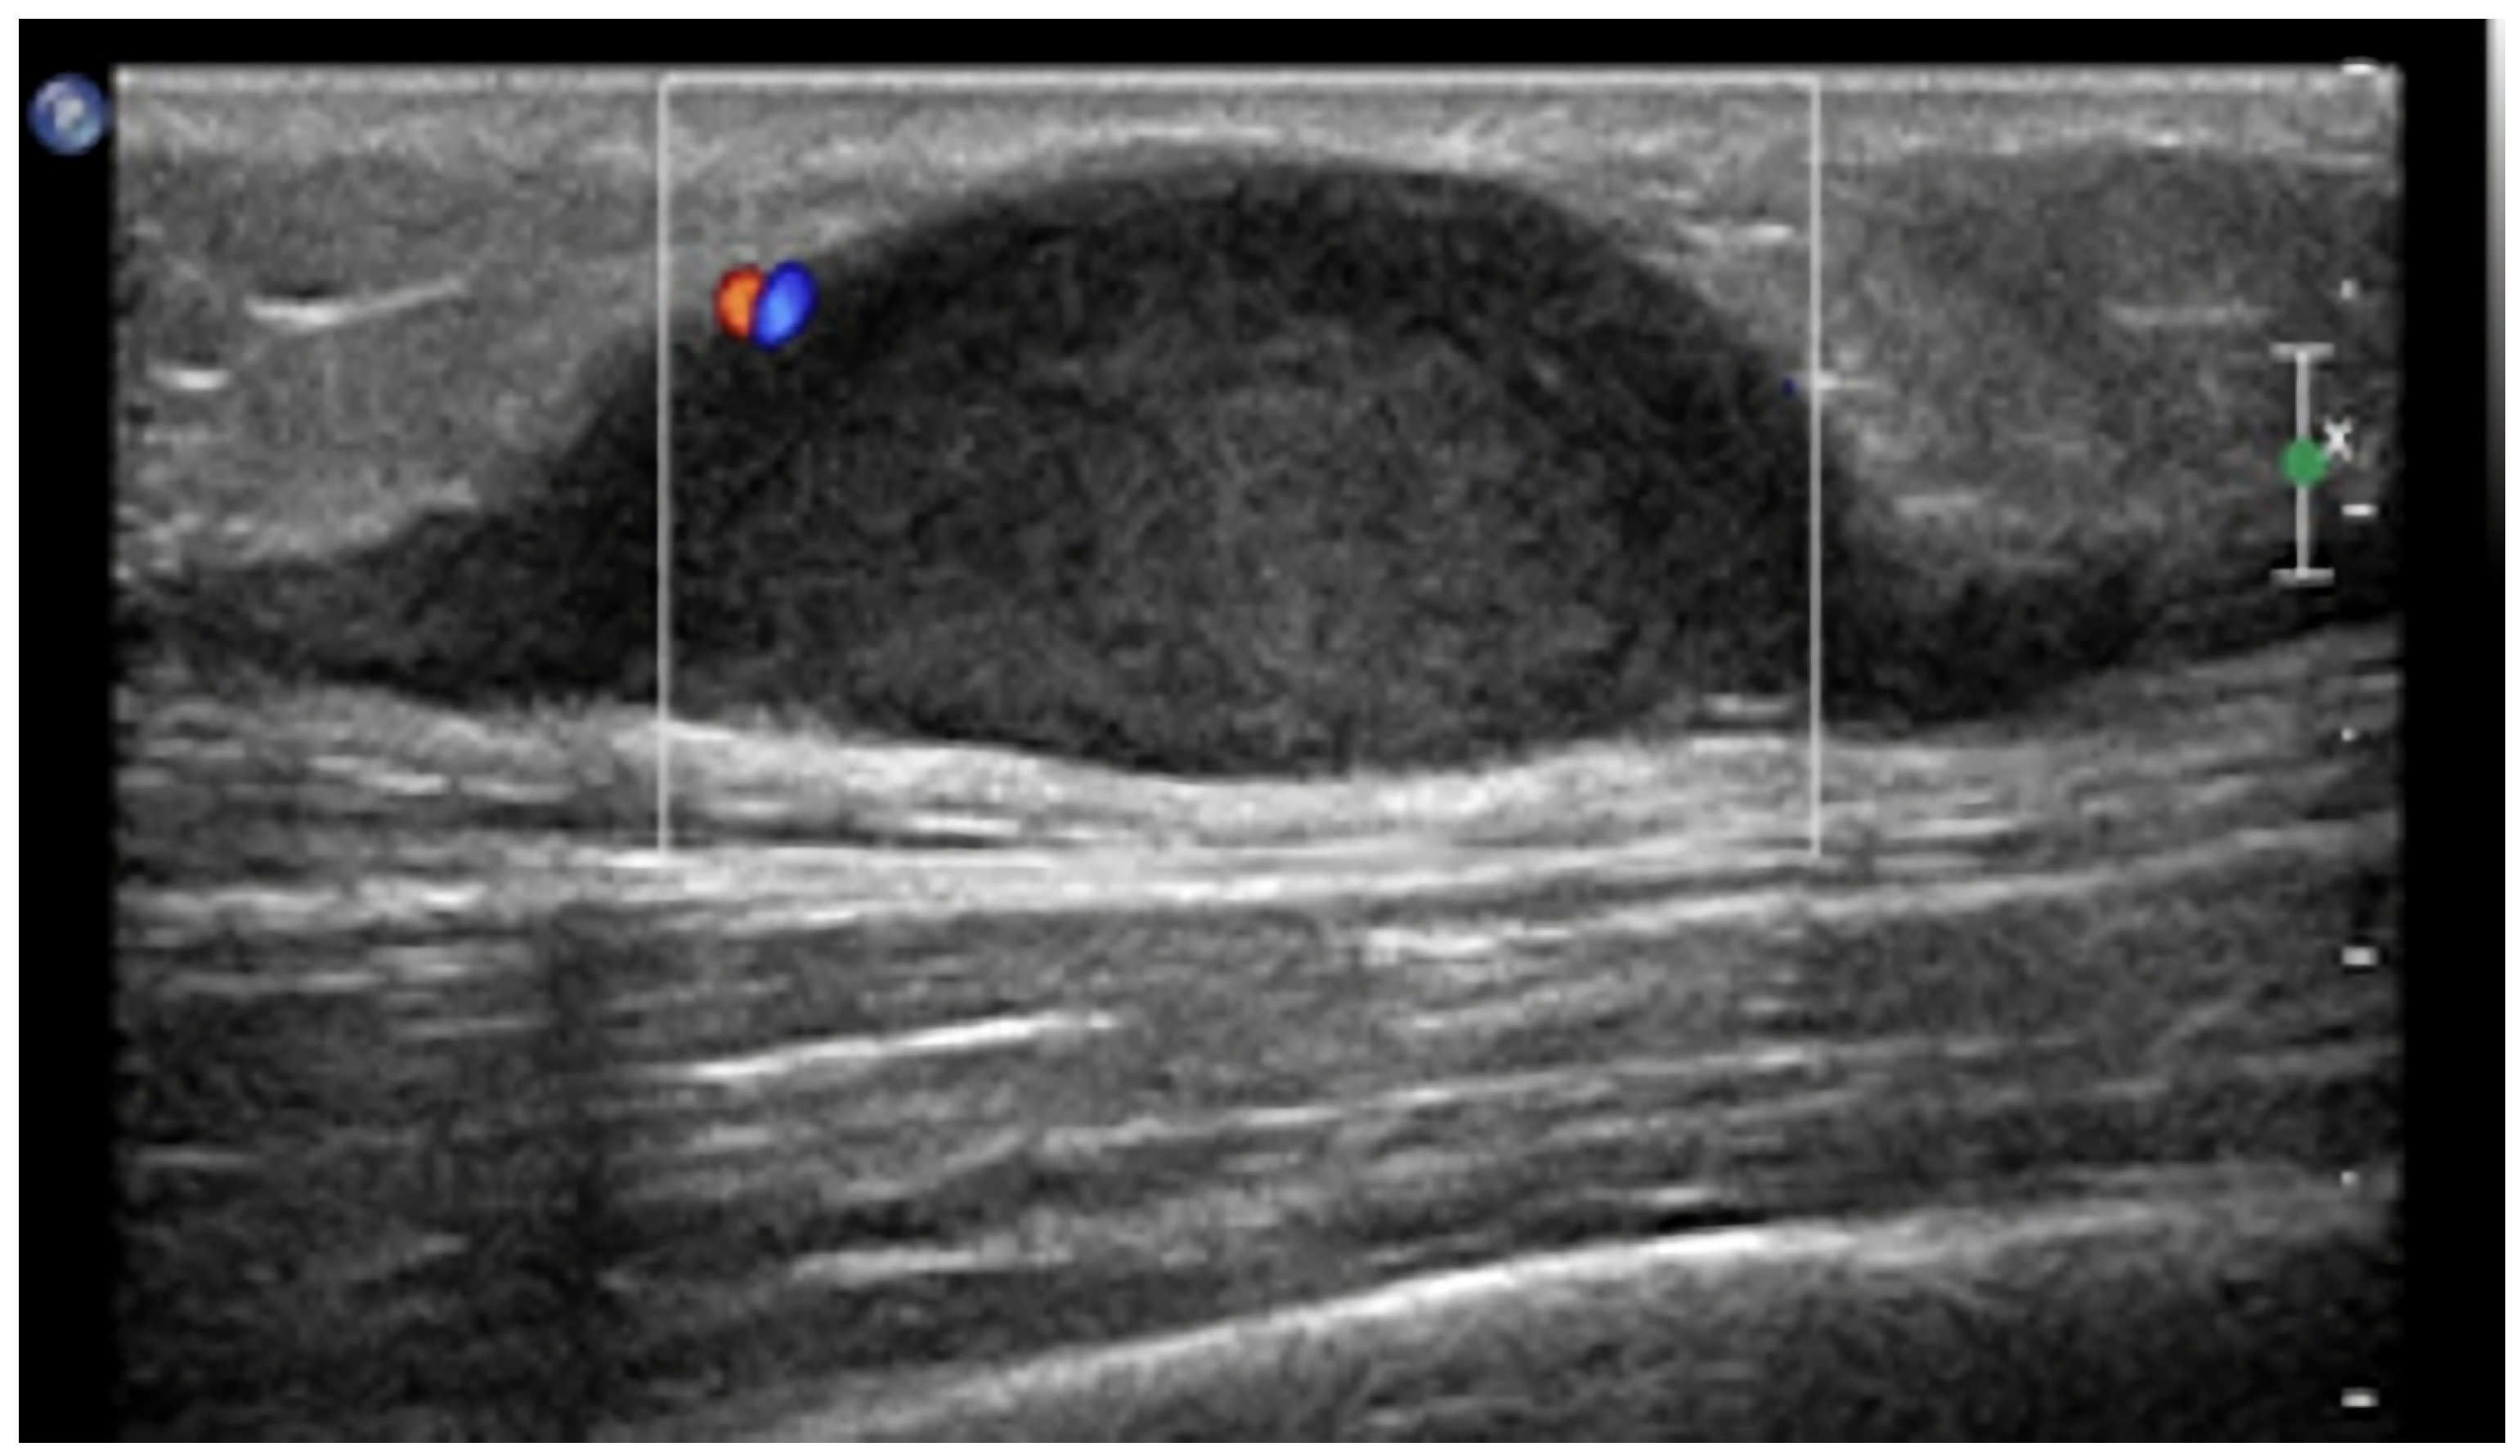

- Gastrointestinal Stromal Tumors (GIST): either primary (extraintestinal GIST, “EGIST”) [25,26] or secondary GIST of the abdominal wall are rare. When extended (>5 cm), GIST may have an aggressive behavior [25]. CT is the imaging modality of choice, showing heterogeneous vivid enhancement, and variable amount of necrosis. Peculiar findings include calcifications and cystic degeneration [27,28,29].